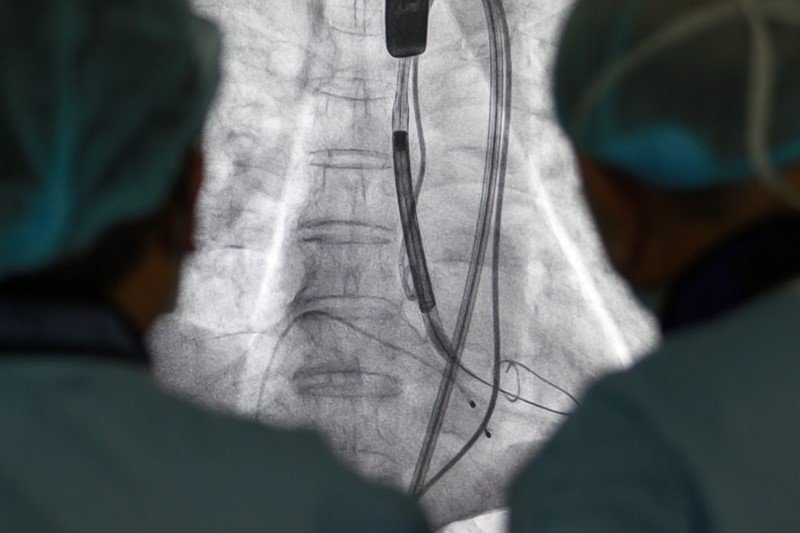

Heart valve repair without openheart surgery ISRAEL21c

Can You Replace A Heart Valve Without Surgery . A minimally invasive procedure to replace a stiff, failing aortic valve offers a shorter, easier recovery than surgical replacement. View an animation of valvuloplasty. How to treat aortic valve stenosis without surgery. Known as tavr, it's currently approved. Called transcatheter aortic valve replacement, or tavr, the approach can be used in patients who are at high or moderate risk of developing complications if they undergo traditional surgery. You may even know people who have had this procedure performed. But it is not a replacement for heart valve. Balloon valvuloplasty can improve blood flow and may help delay valve replacement. Having an aortic valve repaired without surgery is an increasingly common.

A minimally invasive procedure to replace a stiff, failing aortic valve offers a shorter, easier recovery than surgical replacement. How to treat aortic valve stenosis without surgery. Having an aortic valve repaired without surgery is an increasingly common. You may even know people who have had this procedure performed. Called transcatheter aortic valve replacement, or tavr, the approach can be used in patients who are at high or moderate risk of developing complications if they undergo traditional surgery. Balloon valvuloplasty can improve blood flow and may help delay valve replacement. Known as tavr, it's currently approved. View an animation of valvuloplasty. But it is not a replacement for heart valve.